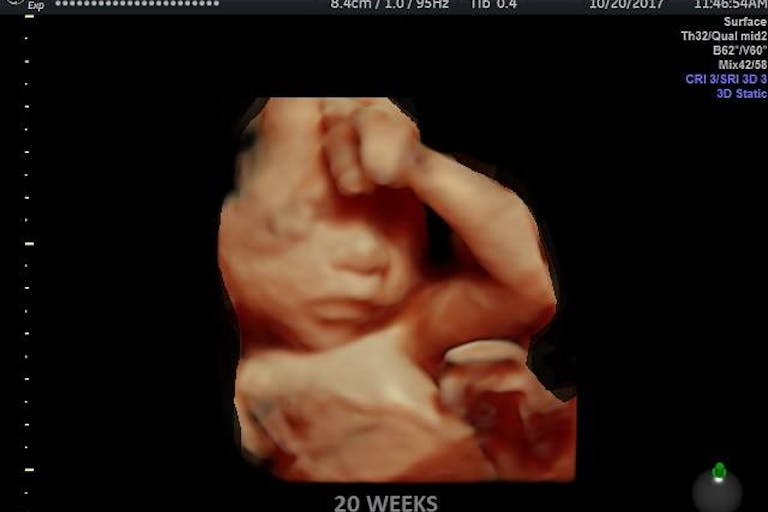

A bill banning abortions beyond 20 weeks has passed the Mississippi House and now makes its way to the Senate, offering hope for life for Mississippi babies aborted even beyond viability.

Of the almost 2,200 abortions in Mississippi in its last reported year, only two were listed as being beyond 21 weeks, but the ban would ensure that these late-term abortions are prevented.